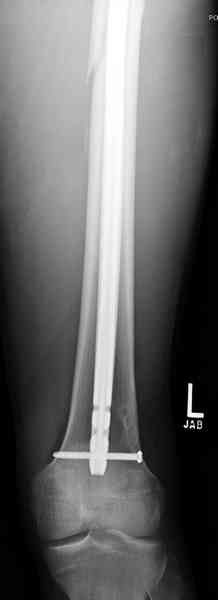

В нашем случае 21 летний боец уличного фронта, фиксацию провели на следующий день, зафиксирован интрамедуллярным штифтом. Не стали делать первичную хирургическую обработку точечной раны, зафиксирован как есть. Клинические снимки: